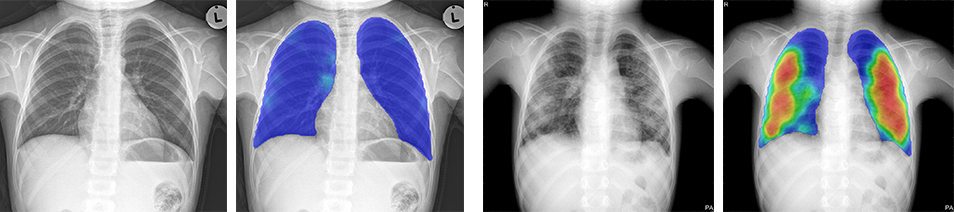

The input and output are still the same: CAD4TB processes frontal chest radiographs from any type of digital X-ray equipment and produces a heatmap, indicating with colours which parts of the lungs are likely abnormal, and a score between 0 and 100. The higher the score, the more likely that the subject on the image has tuberculosis (TB).

Figure 3. Two examples of chest radiographs of children both four years old. The left image is normal, and no abnormal regions are seen in the heatmap. The score of CAD4TB version 6 for this case is 22. The right image has clear abnormalities, accurately detected by CAD4TB 6. The image gets a score of 86.